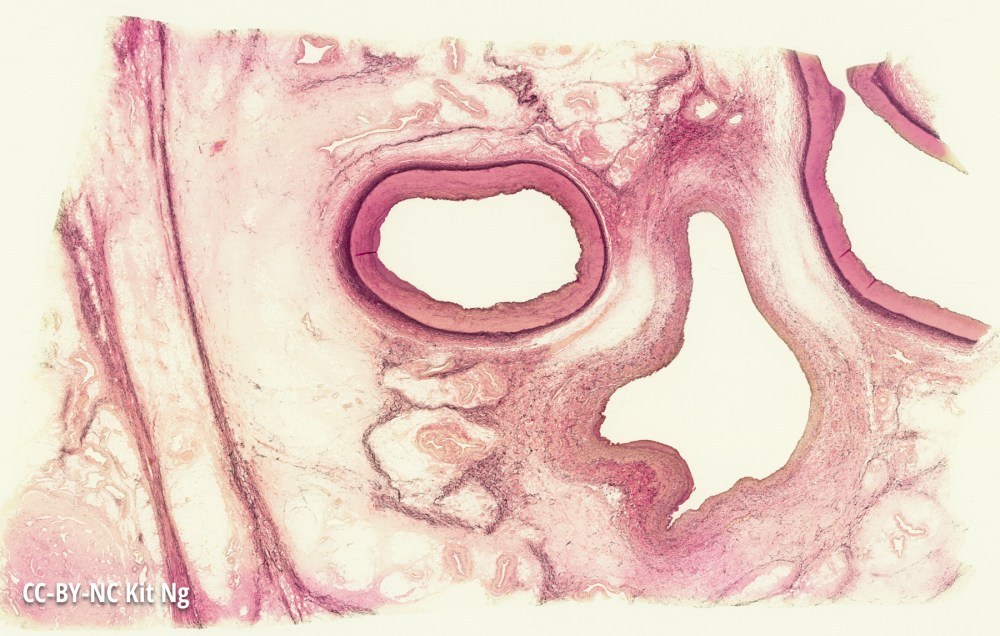

Images Artery vs. Vein Low magnification picture showing the differences (and similarities) between an artery and a vein. Picture of an artery (left) and a vein (right) (TM: ~2.5x, picture taken with a Nikon Coolscan IV slide scanner) Share this: Email a link to a friend (Opens in new window) Email Share on X (Opens in new window) X Share on Facebook (Opens in new window) Facebook Like Loading...